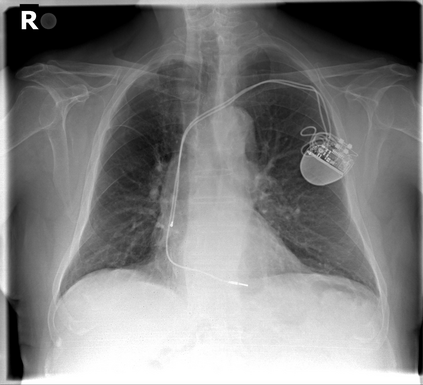

The evaluation of infectious disease processes on radiologic images is an important and challenging task in medical image analysis. Pulmonary infections can often be best imaged and evaluated through computed tomography (CT) scans, which are often not available in low-resource environments and difficult to obtain for critically ill patients. On the other hand, X-ray, a different type of imaging procedure, is inexpensive, often available at the bedside and more widely available, but offers a simpler, two dimensional image. We show that by relying on a model that learns to generate CT images from X-rays synthetically, we can improve the automatic disease classification accuracy and provide clinicians with a different look at the pulmonary disease process. Specifically, we investigate Tuberculosis (TB), a deadly bacterial infectious disease that predominantly affects the lungs, but also other organ systems. We show that relying on synthetically generated CT improves TB identification by 7.50% and distinguishes TB properties up to 12.16% better than the X-ray baseline.